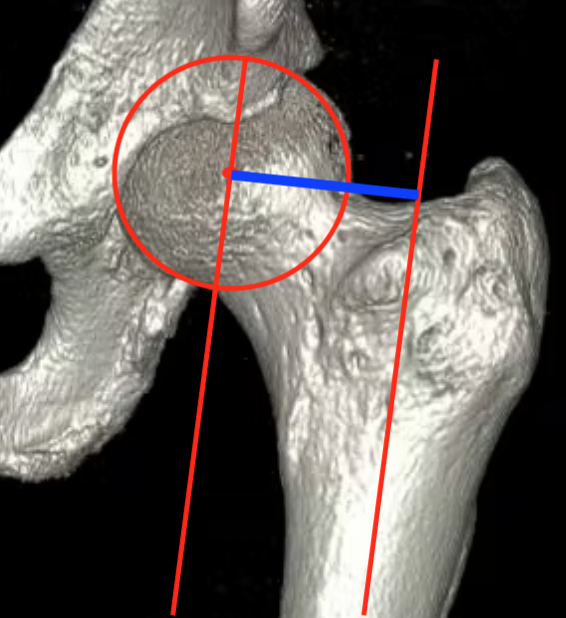

Femoral offset

- perpendicular distance

- from the centre of the femoral head

- to the long axis of the femur

Femoral offsetFemoral offset